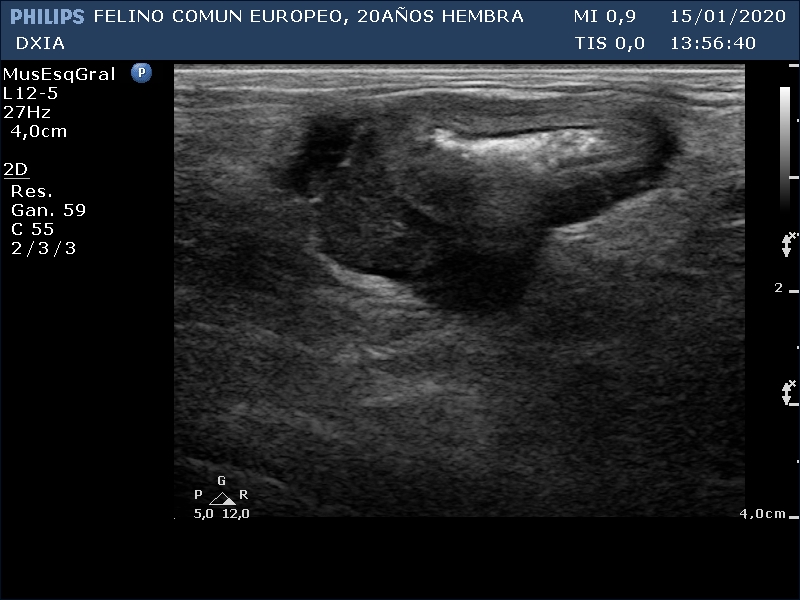

FRANGELICA

Se realiza ecografía y se observa alteración compatible con neoformación en asa del intestino delgado.

Asa del ID con aumento de grosor de su pared, pérdida de estructura en capas. Neoformación hipoecogénica.

Asa del ID con neoformación sin definición de capas intestinales.